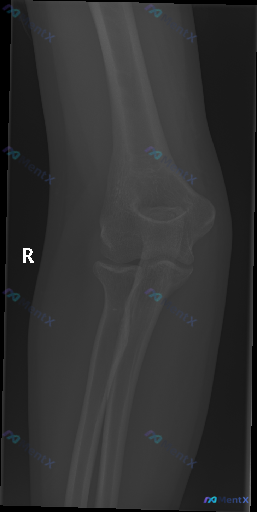

整理到一份影像分析的讨论材料,觉得挺有意思的,来问问大家的第一反应。 前提:用户明确说“这张图像存在异常”,然后给出了一张右侧肘关节侧位X光片的分析。 先放影像报告里的“阴性描述”: - 骨皮质连续,肱骨远端、桡骨头颈、尺骨鹰嘴冠突都没见明确断裂线 - 前脂肪垫征正常,后脂肪垫征阴性,关节腔好像没有...